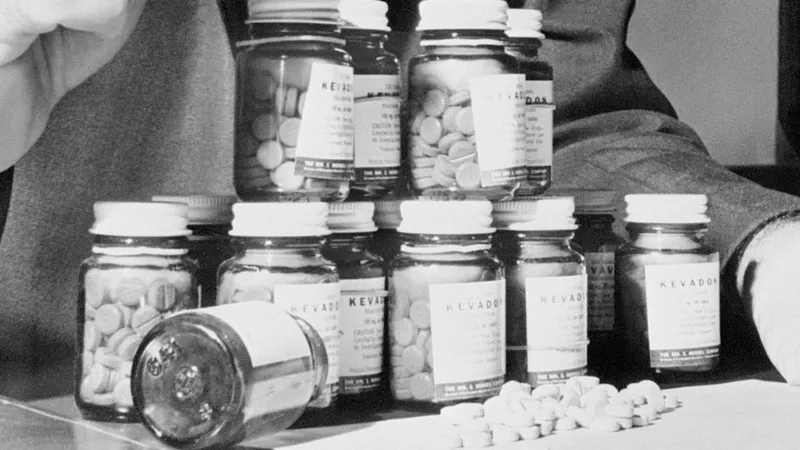

Se trataba de un fármaco que inicialmente se había comercializado como sedante en Europa, a finales de los años 50, y después para aliviar las náuseas durante el embarazo.

Para 1960, el medicamento era accesible en decenas de naciones.

Merrell buscaba lanzar al mercado el producto que había sido creado por la farmacéutica alemana Chemie Grunenthal.

Miles de niños de más de 45 países sufrieron malformaciones después de que sus madres ingirieran talidomida en el embarazo.

“Hubo alrededor de una docena y media de niños nacidos en Estados Unidos con los efectos de la talidomida, (porque) el fármaco había sido distribuido legalmente para fines de investigación”, indica la FDA.

La Asociación Médica de EE.UU. analizó la talidomida y sus efectos. En esta foto, el doctor Samuel Andelman, comisionado de Salud de Chicago en 1960, mostraba algunas de las pastillas recuperadas por el Departamento de Salud de EE.UU.

“Como el fármaco se comercializó con diferentes nombres en 49 países, tomó cinco años hacer la conexión entre la talidomida ingerida por embarazadas y el impacto en sus hijos”.